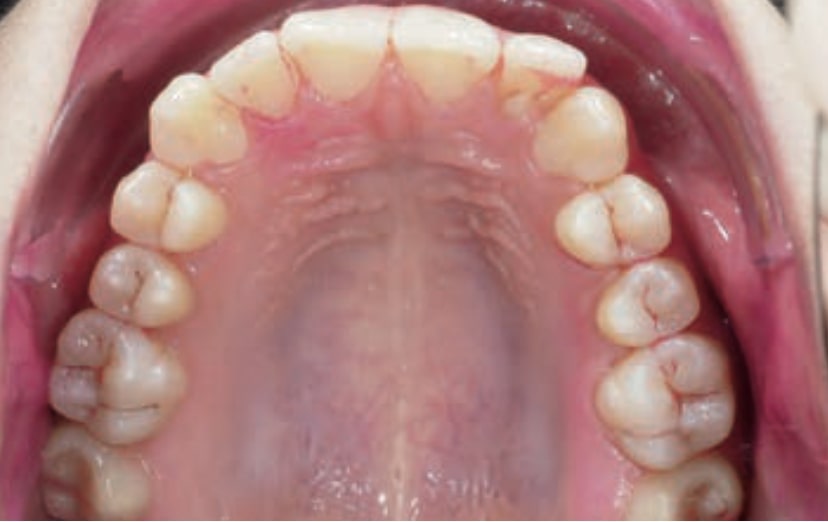

Chief complaint: The patient, a 19-year-old woman, was evaluated to undergo orthodontic treatment using the Angel Aligner Pro system. She presents with a skeletal Class III, mesofacial, with a dental Class III malocclusion and a 2 mm deviation of the lower midline to the left. Teeth 33 and 43 are out of the arch and cortical bone, with a crossbite issue on tooth 33. Fortunately, no functional issues affecting swallowing or breathing have been detected. The patient’s motivation for starting treatment was a general review of her dental and aesthetic health. The soft tissue analysis reveals mandibular protrusion that influences her facial profile. This diagnosis highlights the need for a comprehensive approach to address dental and skeletal misalignments, improving both the patient’s functionality and facial aesthetics.

- Dental Class III, 2 mm deviation of the lower midline to the left. 33 and 43 out of the arch and the cortical bone.

- Crossbite of 33.

- Distalize third and fourth quadrant

- Distalization of the Third and Fourth Quadrants: Move the teeth distally in these quadrants to achieve a Class I relationship using the A8 protocol, improving the patient’s dental alignment and occlusion.